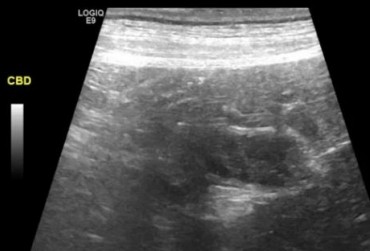

Określenie „rozpoznanie cioci Minnie” pochodzi ze Stanów Zjednoczonych i jest żartobliwym określeniem rozpoznania patognomonicznego, stosowanym głównie przez radiologów. Zwrot ten stał się popularny w latach 90. XX w. za sprawą strony internetowej o takim tytule. Obecnie to określenie stosuje się również w metodologii nauczania klinicznego. W artykule przedstawiono przypadki rozpoznań „cioci Minnie” z własnego archiwum ultrasonografii jamy brzusznej małych zwierząt.